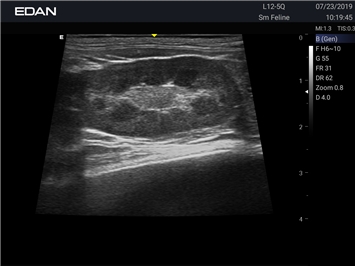

Ветеринарный ультразвук одним нажатием. Система Acclarix AX2 VET разработана с целью обеспечить бескомпромиссную производительность по доступной цене. Наличие уникальных двойных аккумуляторов в легком корпусе массой 4,5 кг из магниевого сплава позволяет системе Acclarix AX2 VET удовлетворять все потребности ветеринарных исследований, сохранив низкую стоимость.

EDAN Acclarix AX2 VET представляет собой специализированную ветеринарную ультразвуковую систему, сочетающую высокую производительность с доступной ценой. Благодаря продуманной конструкции и передовым технологиям, система обеспечивает качественную диагностику животных различных видов.

• Высокое разрешение для детальной диагностики

• Улучшенная визуализация глубоко расположенных органов

• Технология адаптивной визуализации тканей:

• Непрерывная автоматическая оптимизация изображения

• Адаптация к особенностям анатомии разных видов животных

• Повышенная точность исследований